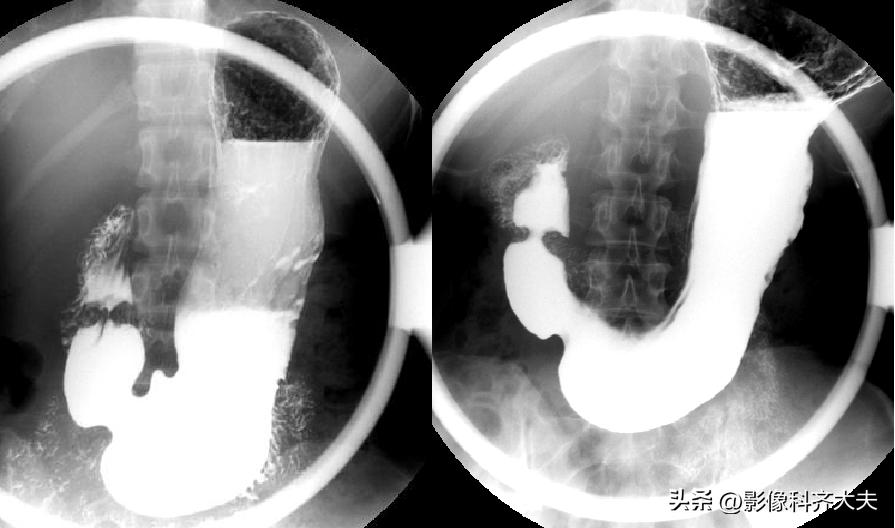

标准体位图像

食管双对比相(站立右前斜位)

食管充盈相或粘膜相(站立右前斜位)

十二指肠球和圈充盈相

十二指肠球和圈双对比相

十二指肠球部及胃窦部加压相